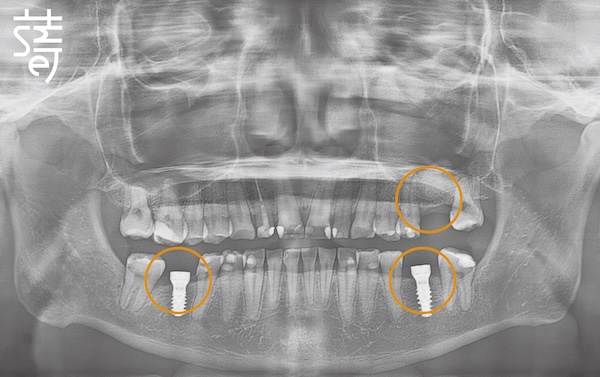

第二階段:植牙重建缺牙區 Stage Two: Implants for Missing Molars

針對缺牙已久的後牙區進行植牙,恢復後牙支撐,避免整體咬合繼續崩塌,讓口腔受力更均衡。

Implants were placed in the long-missing molar areas to restore support, prevent further bite collapse, and balance oral forces.

從矯正、植牙、臨時假牙的調整,到最終假牙的完成,每一步都凝聚著薛醫師的專注與團隊的細心。透過 Modjaw 的動態咬合紀錄與國際專家的臨床經驗,蒔美讓李先生的笑容不只漂亮,更兼具穩定與健康。

From alignment, implants, and temporary prosthetic adjustments to the final restoration, every step reflected Dr. Xue’s focus and the team’s care. With Modjaw’s dynamic bite records and international expertise, Smile ensured Mr. Li’s smile was not only beautiful but stable and healthy.